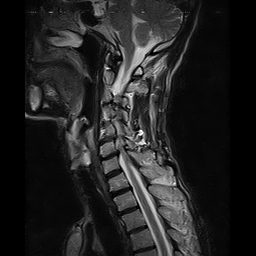

REPORT:

The imaged soft tissues show no abnormalities .

The visualized spinal cord is normal .

Predense distance is normal .

Paravertebral stripe is normal in shape and signal intensity .

– Cervicothoracic scoliosis

– C4/C5/C6 spondylosis – discs space narrowing , dehydration , bulging , thecal compression & canal – stenosis

– C6/C7 spondylosis – disc space narrowing , dehydration , bulging & thecal compression

– Mid thoracic spondylosis – disc space narrowing , dehydration , bulging & thecal indentation

– T1/T2 spondylosis – disc space narrowing , dehydration & bulging